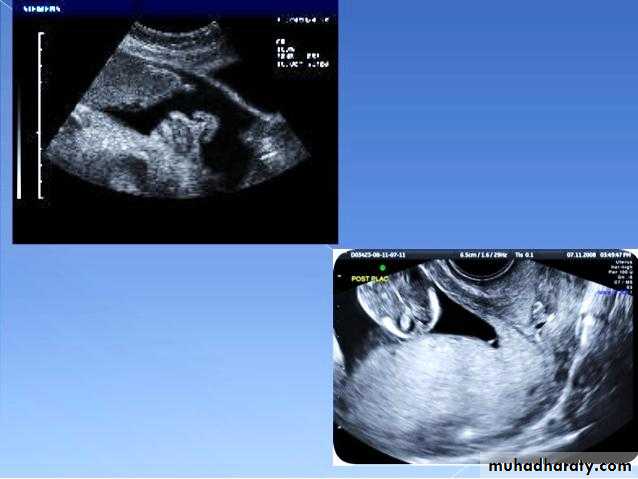

Male or female